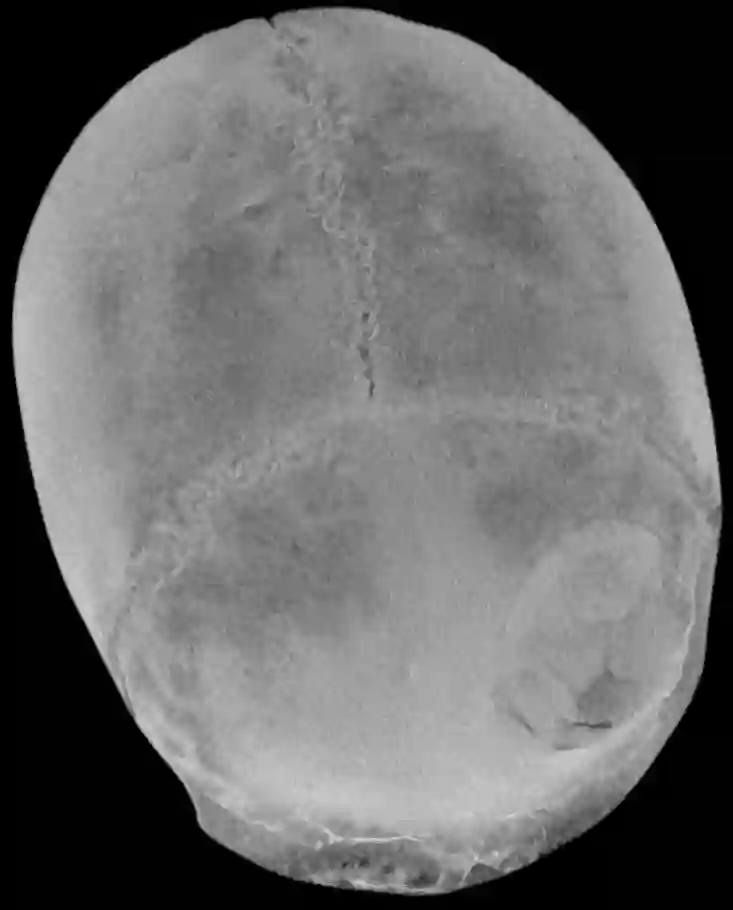

CT Rekonstruktion einer Impressionsfraktur

CT Rekonstruktion einer Impressionsfraktur.